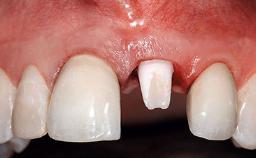

Replacement of an Upper Right Central Incisor with Root Resorption: Ridge Preservation, Early Placement of an RC Bone Level Implant

A 49-year-old female patient was referred for implant therapy to replace the upper right central incisor (tooth 11). The tooth had been assessed by an endodontist who diagnosed a vertical fracture of the root. The tooth had a hopeless prognosis and needed to be extracted. The patient was healthy and was not taking any medications. She was allergic to penicillin. The patient had high esthetic demands but her expectations were realistic. The extraoral examination revealed no facial asymmetries. The right temporomandibular joint demonstrated an opening click but was otherwise asymptomatic. The lip line was high with a significant gingival display.